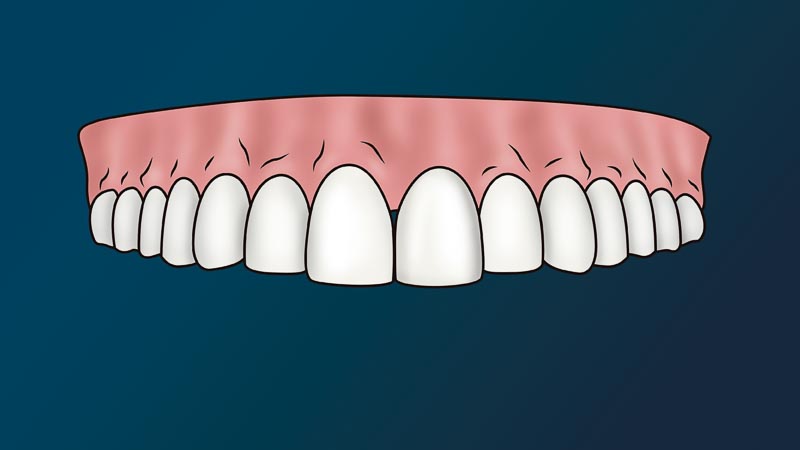

The most viable solution to a missing tooth is to get a dental implant.

The dentist will attach to your jaw a metal root (implant) and place on top a fake tooth (crown). We call this procedure, a dental implant. Since this procedure is non-life threatening and non-essential to one’s immediate health, it considered a cosmetic procedure. In other words, medical or dental insurance policies don’t cover this procedure.